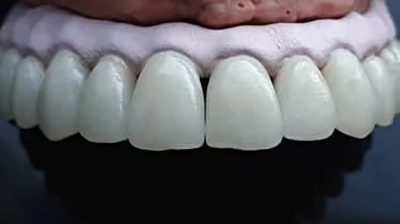

Металлокерамическая коронка выглядит как колпачок, облицованный керамической массой. Готовая коронка надевается на подготовленный зуб. Каркас изготавливается из металлических сплавов. Именно на него приходится вся нагрузка и функция сохранения корня. В нашей клинике металлический каркас изготавливается на немецком цифровом оборудовании с применением 3D технологий. Все происходит автоматически — это гарантирует качественное изготовление каркаса, в отличии от устаревшего способа изготовления методом литья.

Снаружи каркас покрыт слоем керамической массы. По цвету керамика полностью идентична натуральному тону эмали и подбирается индивидуально под каждого пациента.